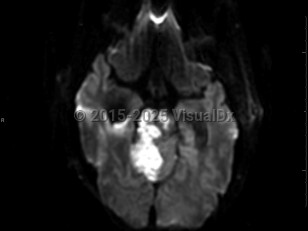

Brain stem stroke

Synopsis